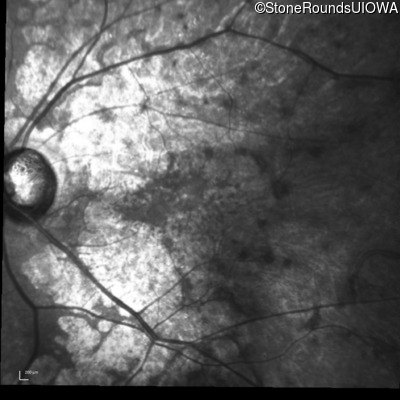

Infrared Fundus Photograph - Left - 20/80 -1

Exemplar